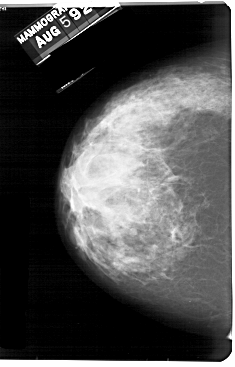

A_1693_1.LEFT_CC

LEFT_CC LINES 5491 PIXELS_PER_LINE 3511 BITS_PER_PIXEL 12 RESOLUTION 43.5 NON_OVERLAY